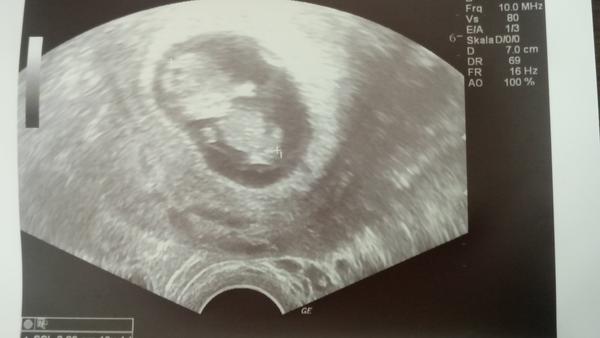

Holky 🙂 30.10 jdeme na potvrzení, natož že jsem dneska cca 4+5 tak mám 3 dny celodenní nevolnost poslední 3 dny bolesti v podbřišku dneska teda i píchání měla jste to nekterá taky tohle na začátku? Dle sestry z hynekologie jsou tyto bolesti normalni ale i tak nikdy jsem to nemela :(